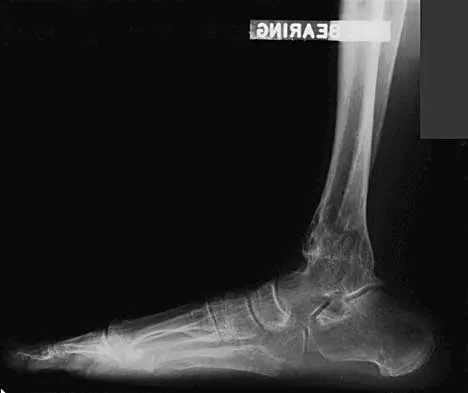

A 28-year-old professional dancer reports a 3-month history of progressive pain in the posterior aspect of the left ankle. Her symptoms are worse when she assumes the en pointe position. Examination reveals tenderness to palpation at the posterolateral aspect of the ankle posterior to the peroneal tendons which is made worse with passive plantar flexion. There is no nodularity, fluctuance, or tenderness of the Achilles tendon. The neurovascular examination is unremarkable. A lateral radiograph and MRI scan are shown in Figures 16a and 16b, respectively. Management should consist of

The imaging studies reveal findings typical of the os trigonum syndrome. This condition results from inflammation between the os trigonum and the adjacent talus. The symptoms of posterior ankle pain are exacerbated by plantar flexion, which stresses the fibrous union between these two bones. Definitive management of the high-level athlete involves excision of the os trigonum from a medial approach, although arthroscopic excision has also been described. The os trigonum is not an intra-articular structure; therefore, ankle arthroscopy is neither diagnostic nor therapeutic. Abramowitz Y, Wollstein R, Barzilay Y, et al: Outcome of resection of a symptomatic os trigonum. J Bone Joint Surg Am 2003;85:1051-1057. Mouhsine E, Crevoisier X, Leyvraz P, et al: Post-traumatic overload or acute syndrome of the os trigonum: A possible cause of posterior ankle impingement. Knee Surg Sports Traumatol Arthrosc 2004;12:250-253.